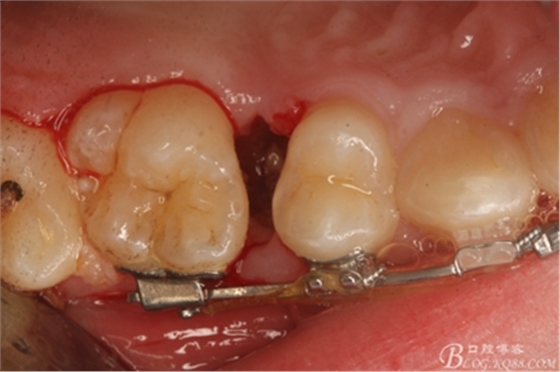

圖11.仔細(xì)考慮之后,在14頰側(cè)做垂直切口,切口長(zhǎng)度僅達(dá)膜齦聯(lián)合處,做小切口。

圖12. 做垂直切口+齦溝內(nèi)切口,形成角形瓣,暴露出15根面。

圖13. 用小球鉆去除約1mm牙槽骨,暴露15牙根面約5mm。